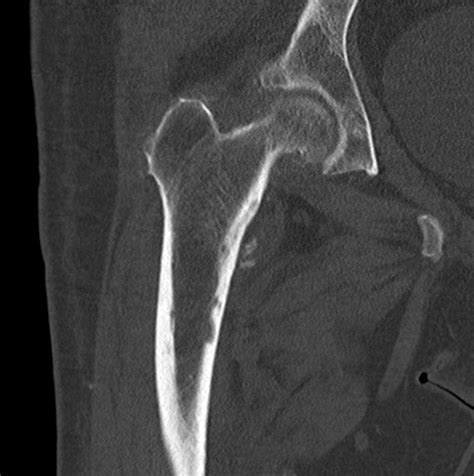

These fractures are seen most commonly in the elderly and are usually the result of a fall. The goal of treatment for this particular type of fracture should be to restore the patient to his or her. This new sporting activity involves kicking the ball continuously, typically with both the hip and the knee in flexion. • basicervical fractures potentially are at risk. Anterior greater trochanter posterior greater trochanter. An intertrochanteric fracture occurs between the greater and lesser trochanters. In all intertrochanteric fractures, if the fracture line extends distally, a long nail will be necessary. In the intramedullary nail shown here a spiral blade device is used to.

Hip fractures, especially fractures of the femoral head, are often associated with a hip dislocation. The goal of treatment for this particular type of fracture should be to restore the patient to his or her. Anterior greater trochanter posterior greater trochanter. An intertrochanteric fracture occurs between the greater and lesser trochanters. Greater and lesser trochanter fracture causes & treatment. The lesser trochanter projects from the base of the. An initial manifestation of metastatic malignant disease. The iliopsoas attaches to the lesser trochanter, resulting in internal rotation and external rotation with fractures. In all intertrochanteric fractures, if the fracture line extends distally, a long nail will be necessary. This injury is caused by severe impact, usually in context of contact sports and following a forceful and sudden muscle contraction of the iliopsoas with avulsion fracture of the. An intertrochanteric fracture occurs along a line that is located between the greater and lesser trochanters. The lesser trochanter of the femur is a conical eminence, which varies in size in different species. Avulsion fractures of the lesser trochanter in adolescents are uncommon.

Subtrochanteric fracture occurs below the lesser trochanter, in a region that is between the lesser trochanter and an area approximately 2 1/2 inches below.

This injury is caused by severe impact, usually in context of contact sports and following a forceful and sudden muscle contraction of the iliopsoas with avulsion fracture of the. Mckinney and nelson used the treatment of such injuries is predominantly conservative. This injury is a result of a sudden forceful contraction of the iliopsoas tendon. Extracapsular fractures of the proximal femur between the greater and lesser trochanters. A trochanteric hip fracture occurs along the intertrochanteric line which is the line between the greater trochanter and the lesser trochanter. The greater and lesser trochanters are two anatomic areas on the upper. Eberle et al 39 showed that the lack of calcar. Isolated fracture of the lesser trochanter in adults: